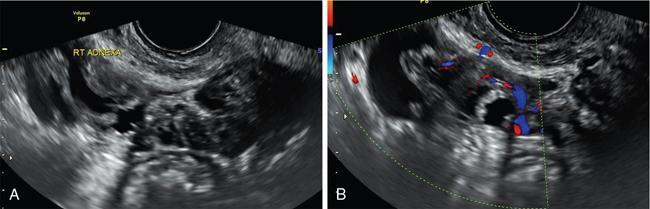

John De Lindsay, Subhashree C SALPINGITIS Salpingitis refers to the diffuse inflammation of the fallopian tubes and can be unilateral or bilateral. It is the most common early form of PID. Salpingitis has the highest risk of infertility and ectopic pregnancies. Coexisting endometritis can be seen in up to 70%–90% of nonobstetric patients. The clinical presentation in salpingitis can be variable, from being asymptomatic to severe pelvic discomfort and tenderness. Poor correlation is often noted between the degree of symptoms and the extent of tubal inflammation. In salpingitis, the fallopian tubes become hyperemic and swollen due to inflammation. With suppurative salpingitis, the lumen of the tube distends with pus and spills over into the peritoneal cavity, coating the serosa of the adjacent uterus and ovary. US maybe used as the first-line imaging modality for evaluating suspected salpingitis. Subtle abnormalities such as fallopian tubal tenderness with tortuosity, increased wall vascularity and tubal thickening of more than 5 mm may be considered pointers towards salpingitis. Salpingitis may be considered on CT when the fallopian tube thickening is more than 5 mm in axial dimension with enhancing walls (Fig. 11.17.1.1). Adjacent peritubal free fluid or cul-de-sac fluid may be other indicators. Fallopian tube thickening is the most specific sign to arrive at a diagnosis of salpingitis (Fig. 11.17.1.1). Chronic salpingitis may present as diffuse tubal irregularity with narrowing or complete obliteration of the tubes. Salpingitis isthmica nodosa is a benign inflammatory process causing nodular scarring of the fallopian tubes. At hysterosalpingography, tubal irregularity and subcentimetric protrusions from the isthmic portion of the tube are seen. PELVIC INFLAMMATORY DISEASE Pelvic infection is one of the most frequent cause of pelvic pain in females. Diagnosis of pelvic inflammatory disease (PID) can be challenging because it mimics other abdominal and pelvic processes. Pelvic ultrasonography is the first line investigation of choice. Multimodality imaging with CT and MRI are required for making a definitive diagnosis and for assessing the extent of disease and complications. PID is a spectrum of disease where microorganisms cause an inflammatory continuum ascending from the lower genital tract to infect the uterus, fallopian tubes, ovaries and may extend to the peritoneal cavity. The infection begins with cervicitis and progresses to endometritis, salpingitis, pyosalpinx, tubo-ovarian complex and ultimately tubo-ovarian abscess (TOA) (Fig. 11.17.2.1). One-third to one-half of cases are due to chlamydia trachomatis or Neisseria gonorrhoeae. However, PID is most commonly (30%–40%) a polymicrobial infection and substantial proportion of cases are nongonococcal and nonchlamydial in origin. It may be due to vaginal flora, anaerobic gram-negative rods and Mycoplasma bacteria. Tuberculosis and actinomycosis occur less frequently. Risk factors for PID include young age, multiple sexual partners, an increased frequency of coitus and the presence of intrauterine contraceptive device. Secondary infection of adnexa from gastrointestinal origin like appendicitis and diverticulitis is also common. Clinical diagnosis of acute PID often presents a challenge due to overlap of symptoms and signs with conditions like endometriosis, appendicitis and ectopic pregnancy. Symptoms: Pelvic pain is the most common symptom, although may be absent or mild in some patients. Mucopurulent vaginal discharge and fever are the other usual symptoms. Signs: Per vaginal examination reveals cervical motion tenderness, uterine and adnexal tenderness. Chronic PID symptoms: Patients may be asymptomatic. They can present with chronic pelvic pain, low back ache, dyspareunia, abnormal vaginal bleeding and vaginal discharge. WBCs on saline microscopy of vaginal secretions, elevated ESR, CRP and leucocytosis. A delay in treatment of PID causes significant reproductive and gynaecologic morbidity, such as infertility, increased risk of ectopic pregnancy, chronic pelvic pain and recurrent infection. Hence there is need for proper and adequate treatment of this condition. Most patients can be treated as out-patients with broad spectrum antibiotics. Hospitalisation is required in severe cases like TOA (Fig. 11.17.2.2). Inflammation of uterine cervix. May be infectious or noninfectious. Infectious cervicitis represents early presentation of PID. USG shows an enlarged cervix and hyperaemic cervical canal. CT and MRI show an enhancing endocervical canal. Cysts can be seen lining the endocervical canal. Cervical stroma is usually intact. Differentiation from cervical malignancy is made by lack of enhancing solid components in the abnormal cervix. Inflammation of the endometrial lining of uterus. Usually occurs during pregnancy or postpartum state or gynaecologic instrumentation. USG imaging findings depend on stage of PID. In early or mild infection, the findings are nonspecific. Endometritis may not exhibit any sonographic findings. A fluid-filled endometrial cavity is suggestive of endometritis in the setting of fever, vaginal discharge and uterine tenderness on physical examination. Intrauterine fluid is a nonspecific finding. Gas in the endometrial cavity will appear as foci of increased echogenicity with posterior dirty shadowing. Presence of gas increases the possibility of infection, though gas in the endometrial cavity can be present postpartum and postinstrumentation. Fluid in cul-de-sac is again a nonspecific finding. Internal echoes within the fluid could suggest infection (or haemorrhage) (Fig. 11.17.2.3A).